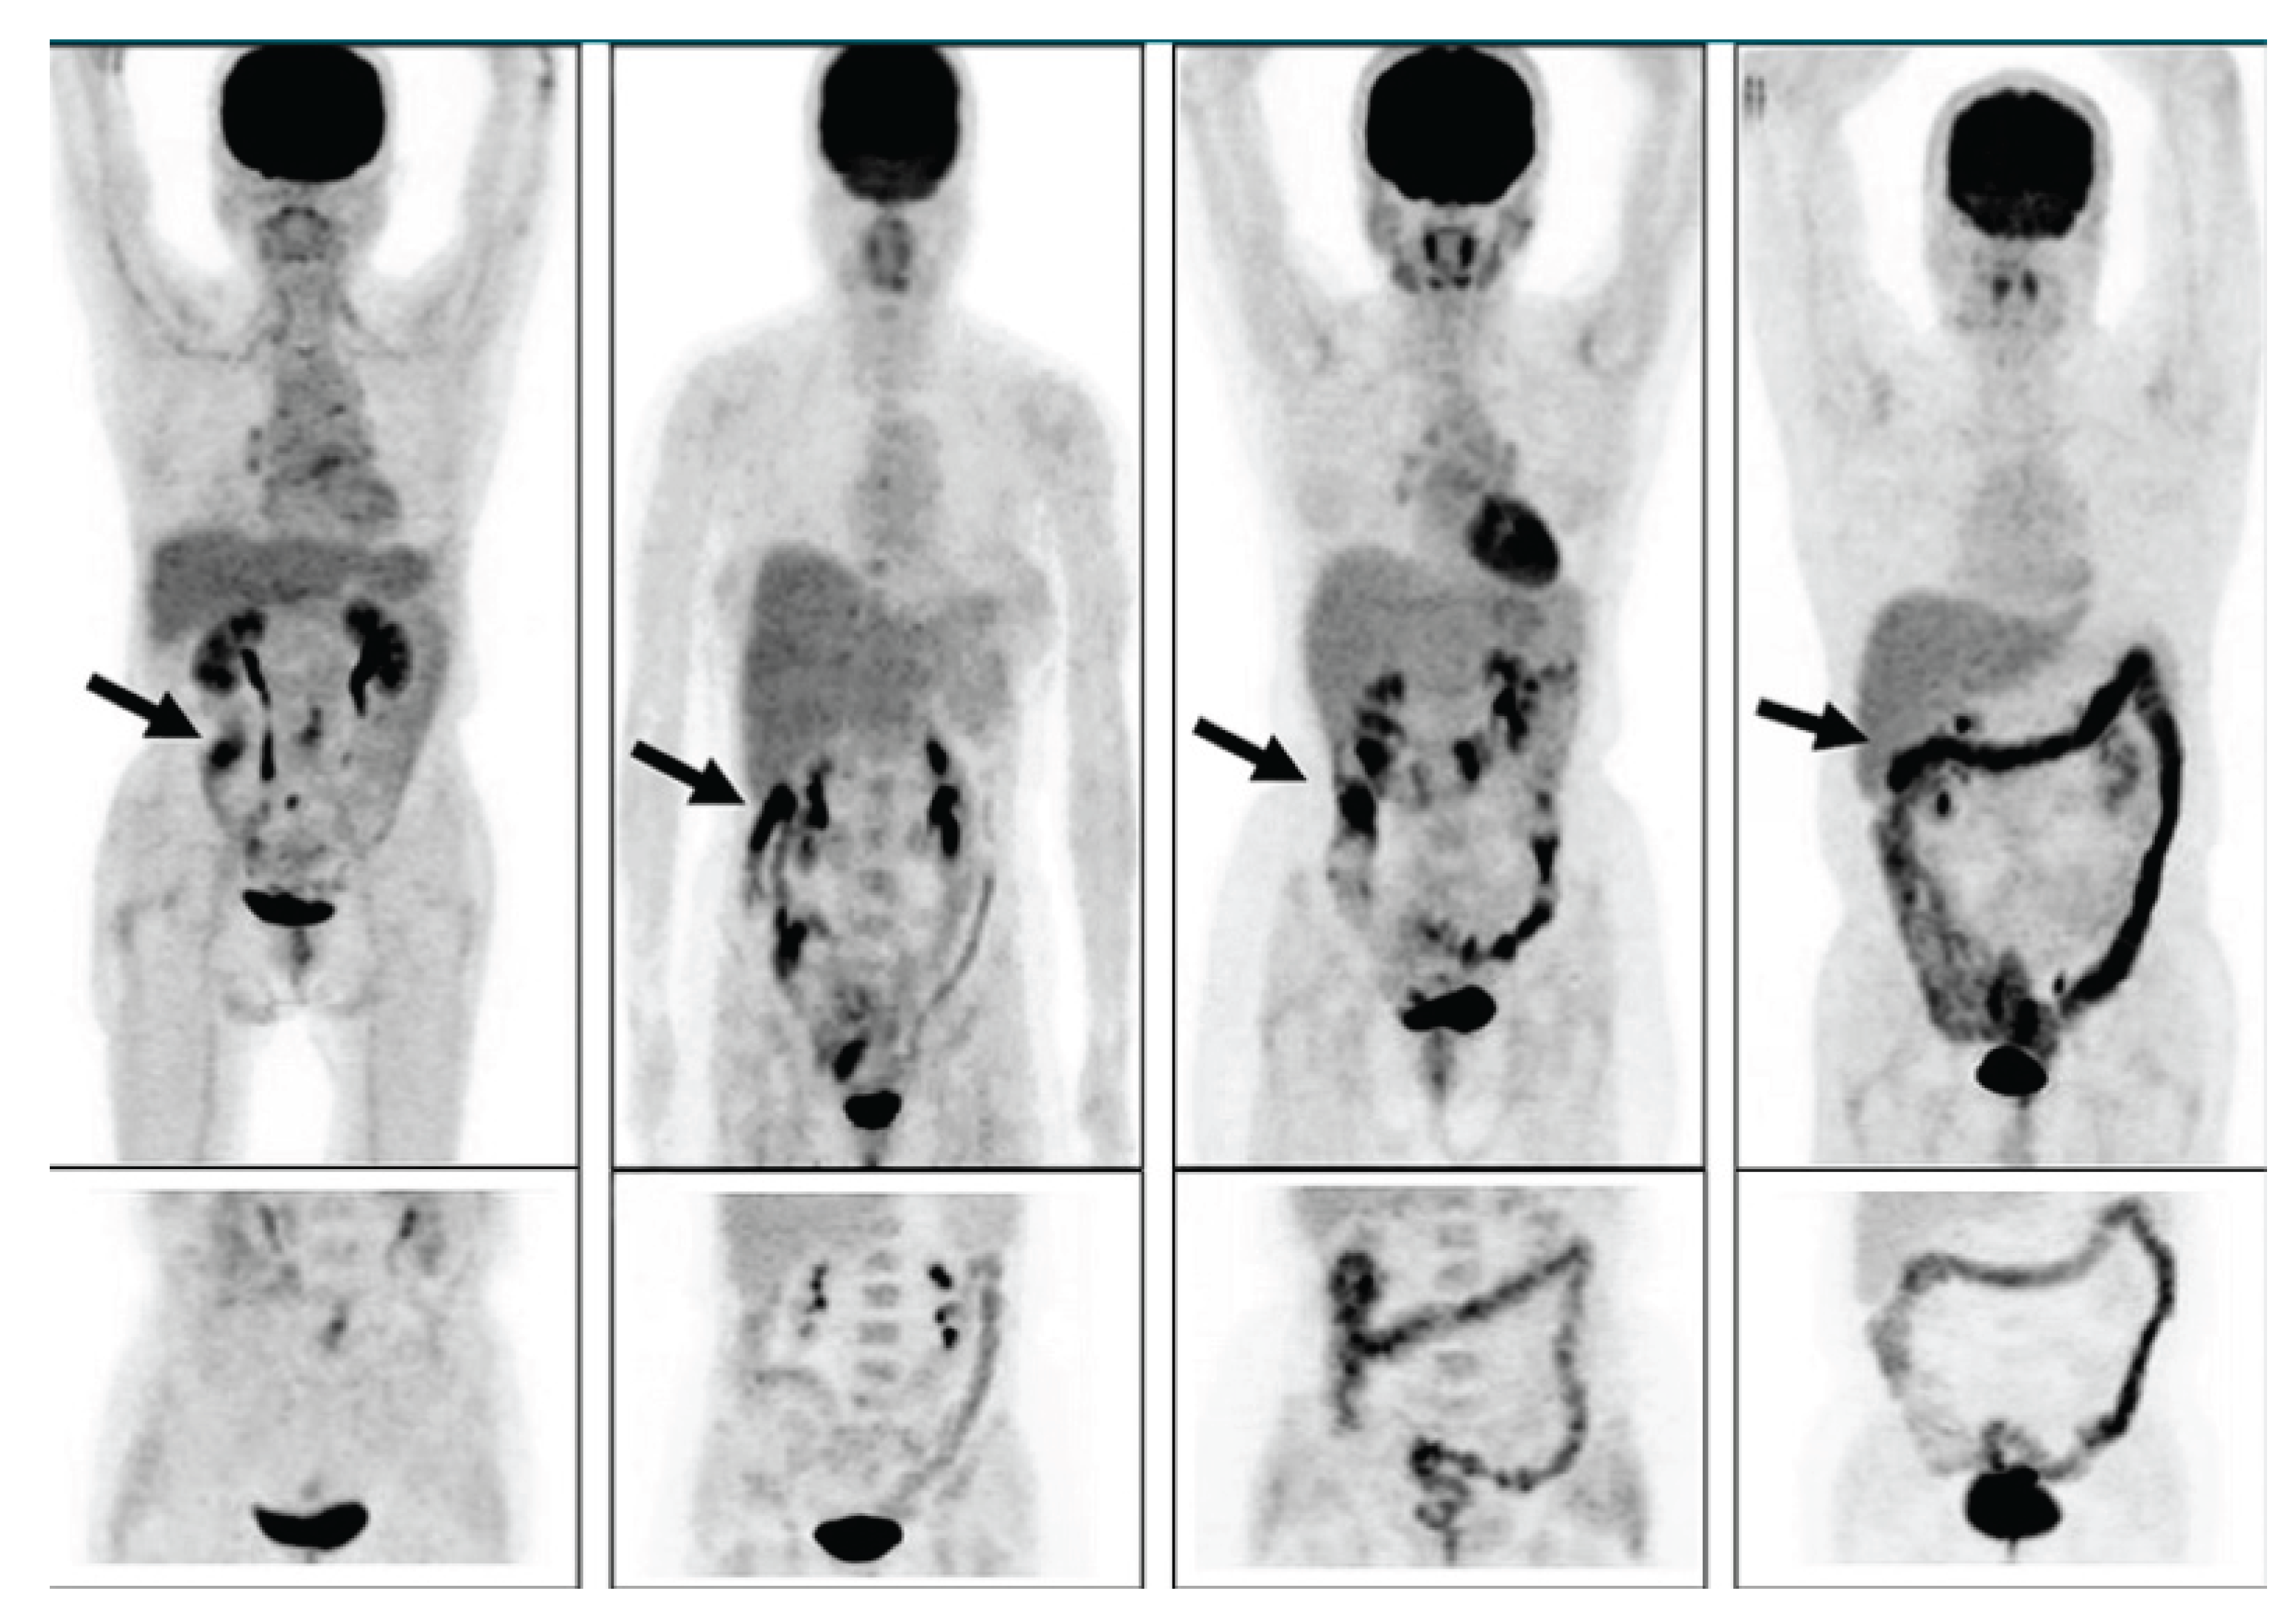

Morita and coworkers [189] by using positron emission tomography (PET)-MRI, recently found that the maximum standardized uptake value (SUVmax) of F18-FDG in the intestine (jejunum, ileum and right or left hemicolon) of metformin- treated diabetics was higher than that of the control group. More importantly, the study permitted to differentiate the SUVmax of the intestinal wall from that of the intestinal lumen. The SUVmax of the intraluminal space in metformin-treated diabetics was greater than that of controls (Figure 2). On the contrary the SUVmax of the intestinal wall was similar in both groups [189]. A temporarily increased accumulation of the injected tracer seems to be observed (Figure 3) also in the liver of metformin-treated diabetics up to 48 hours after interruption of the oral uptake of the drug [189,190,191] suggesting a persisting uptake of the radioactive glucose mediated by circulating insulin as consequence of the ”metabolic starvation”(?) induced by the biguanide.

Figure 3. PET-scan was performed in diabetics at different times after interruption of metformin therapy. In patient 4 interruption time was shorter than 48 hours and showed strong accumulation of the tracer in the colon. From Schreuder N et al. [191].